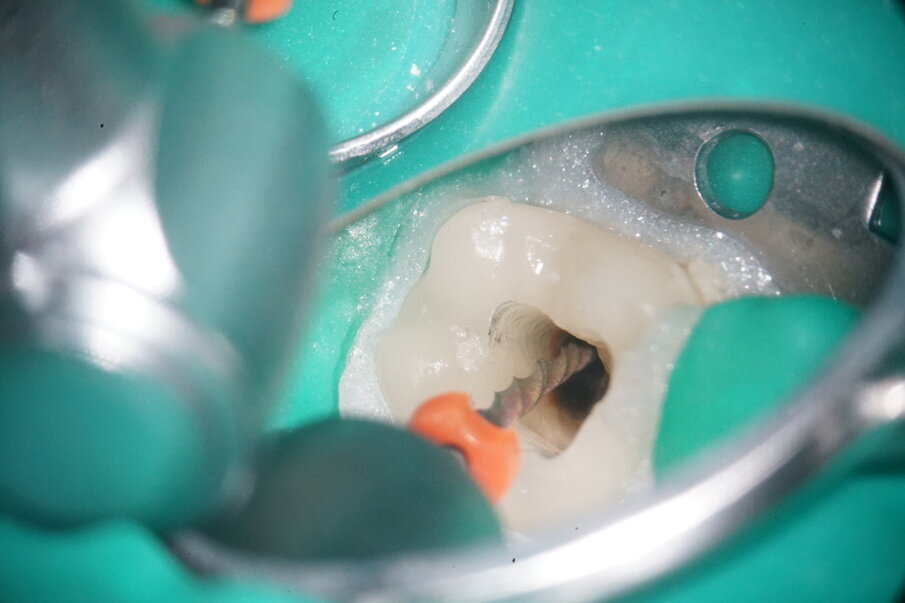

After applying the dental dam and preparing the access cavity, the next step was to remove the existing obturation material (Figs. 3 & 4). A high-speed rotary HyFlex Remover was used for this purpose (Fig. 5). The revision file efficiently removed the materials from the root canal so that additional solvent could be dispensed with during treatment. Unlike in other cases, the plastic carriers in this case were not extracted with an aid, but were machined (see video above). The non-cutting tip of the retreatment file protects the surrounding tooth structure during this procedure, which makes handling even easier.

The remaining apical gutta-percha was removed distally using a reciprocating 25/.06 MicroMega One RECI (Fig. 6). Owing to its cross-sectional design, this instrument features high cutting performance, making it ideal for revision treatment.

Fig. 4: Initial situation of distal canals.